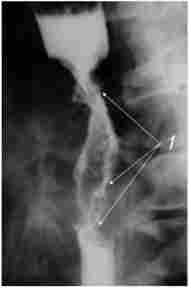

Рентгенограма сунрастенотічного розширення стравоходу

Мал. 103. Рентгенограма сунрастенотічного розширення стравоходу2:

1 - компенсаторное розширення просвіту стравоходу; 2 - пухлина стравоходу

При циркулярному поширенні пухлини стравохід на цій ділянці стає звуженим, утворюючи «раковий канал». Над звуженням, як правило, визначається супрастенотічне розширення (рис. 10.3).